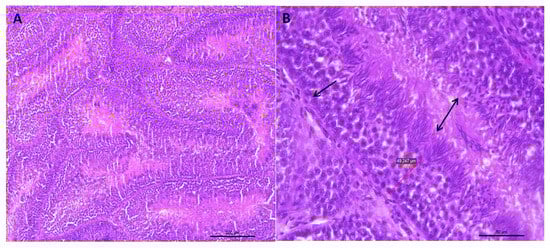

3.1.2. Integrity of the Seminiferous Epithelium